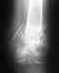

У меня перелом пяточной кости без смещения с 26 апреля,уже месяц в гипсе.Сама нашла рекомендации к использованию ортеза ОТТОБОКК 28F10,удалось его приобрести.Хотела бы получить профессиональную помощь по его сборке и подгонке.Есть ли у вас такая услуга?